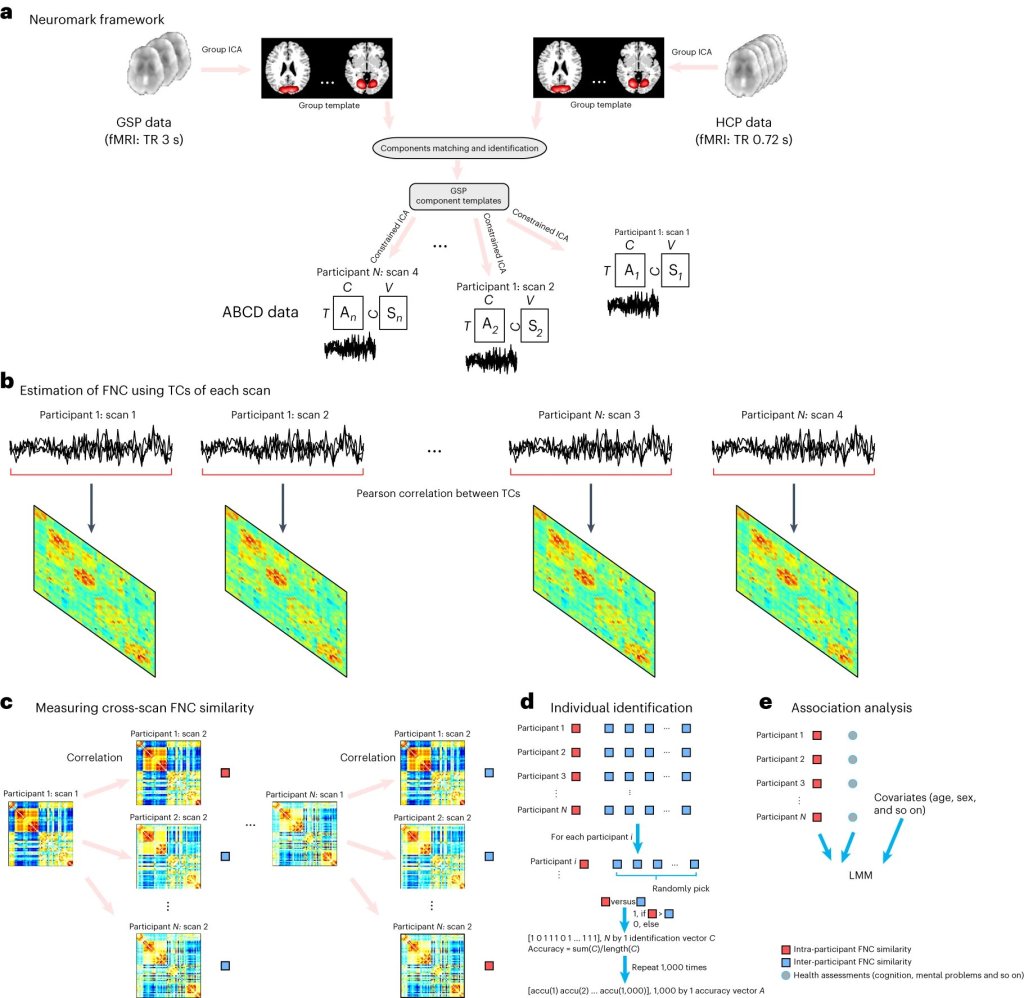

Findings from my own laboratory in 1997 showed that repeated ketamine intake alters the balance between the neurotransmitters dopamine and serotonin in the brain. Ketamine’s interaction with the NMDA receptor for glutamate triggers a surge in glutamate, a neurotransmitter vital for learning and memory. This glutamate surge is thought to promote the growth of new synapses and neural connections, particularly in brain regions associated with mood regulation. Additionally, ketamine disrupts the default mode network (DMN), a brain network linked to rumination and self-referential thinking, which may contribute to its antidepressant effects. Research also suggests that ketamine may stimulate neurogenesis (the growth of new neurons) and promote neuroplasticity (changes in neural connections).

The Promise of Ketamine in Mental Health

When administered at a therapeutic dose ketamine’s rapid antidepressant effects have revolutionized the field of mental health treatment. Studies have shown that a single therapeutic dose of ketamine can alleviate depressive symptoms within hours, offering hope to individuals who have not responded to traditional antidepressants. In fact, so effective is therapeutic ketamine that it has been proposed as a chemical replacement for electroconvulsive therapy (ECT) and it may eventually replace the need for ECT altogether. Beyond depression, ketamine is being investigated for its potential in treating anxiety disorders, PTSD, and addiction.